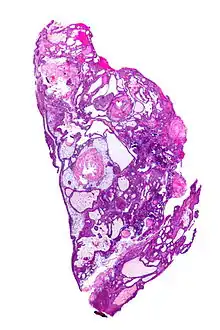

| Very low magnification micrograph of an adamantinomatous craniopharyngioma. HPS stain. | |

On macroscopic examination, craniopharyngiomas are cystic or partially cystic with solid areas. On light microscopy, the cysts are seen to be lined by stratified squamous epithelium. Keratin pearls may also be seen. The cysts are usually filled with a yellow, viscous fluid rich in cholesterol crystals. Of a long list of possible symptoms, the most common presentations include headaches, growth failure, and bitemporal hemianopsia.

Micrograph showing the characteristic features of an adamantinomatous craniopharyngioma - cystic spaces, calcifications, and "wet" keratin, HPS stain